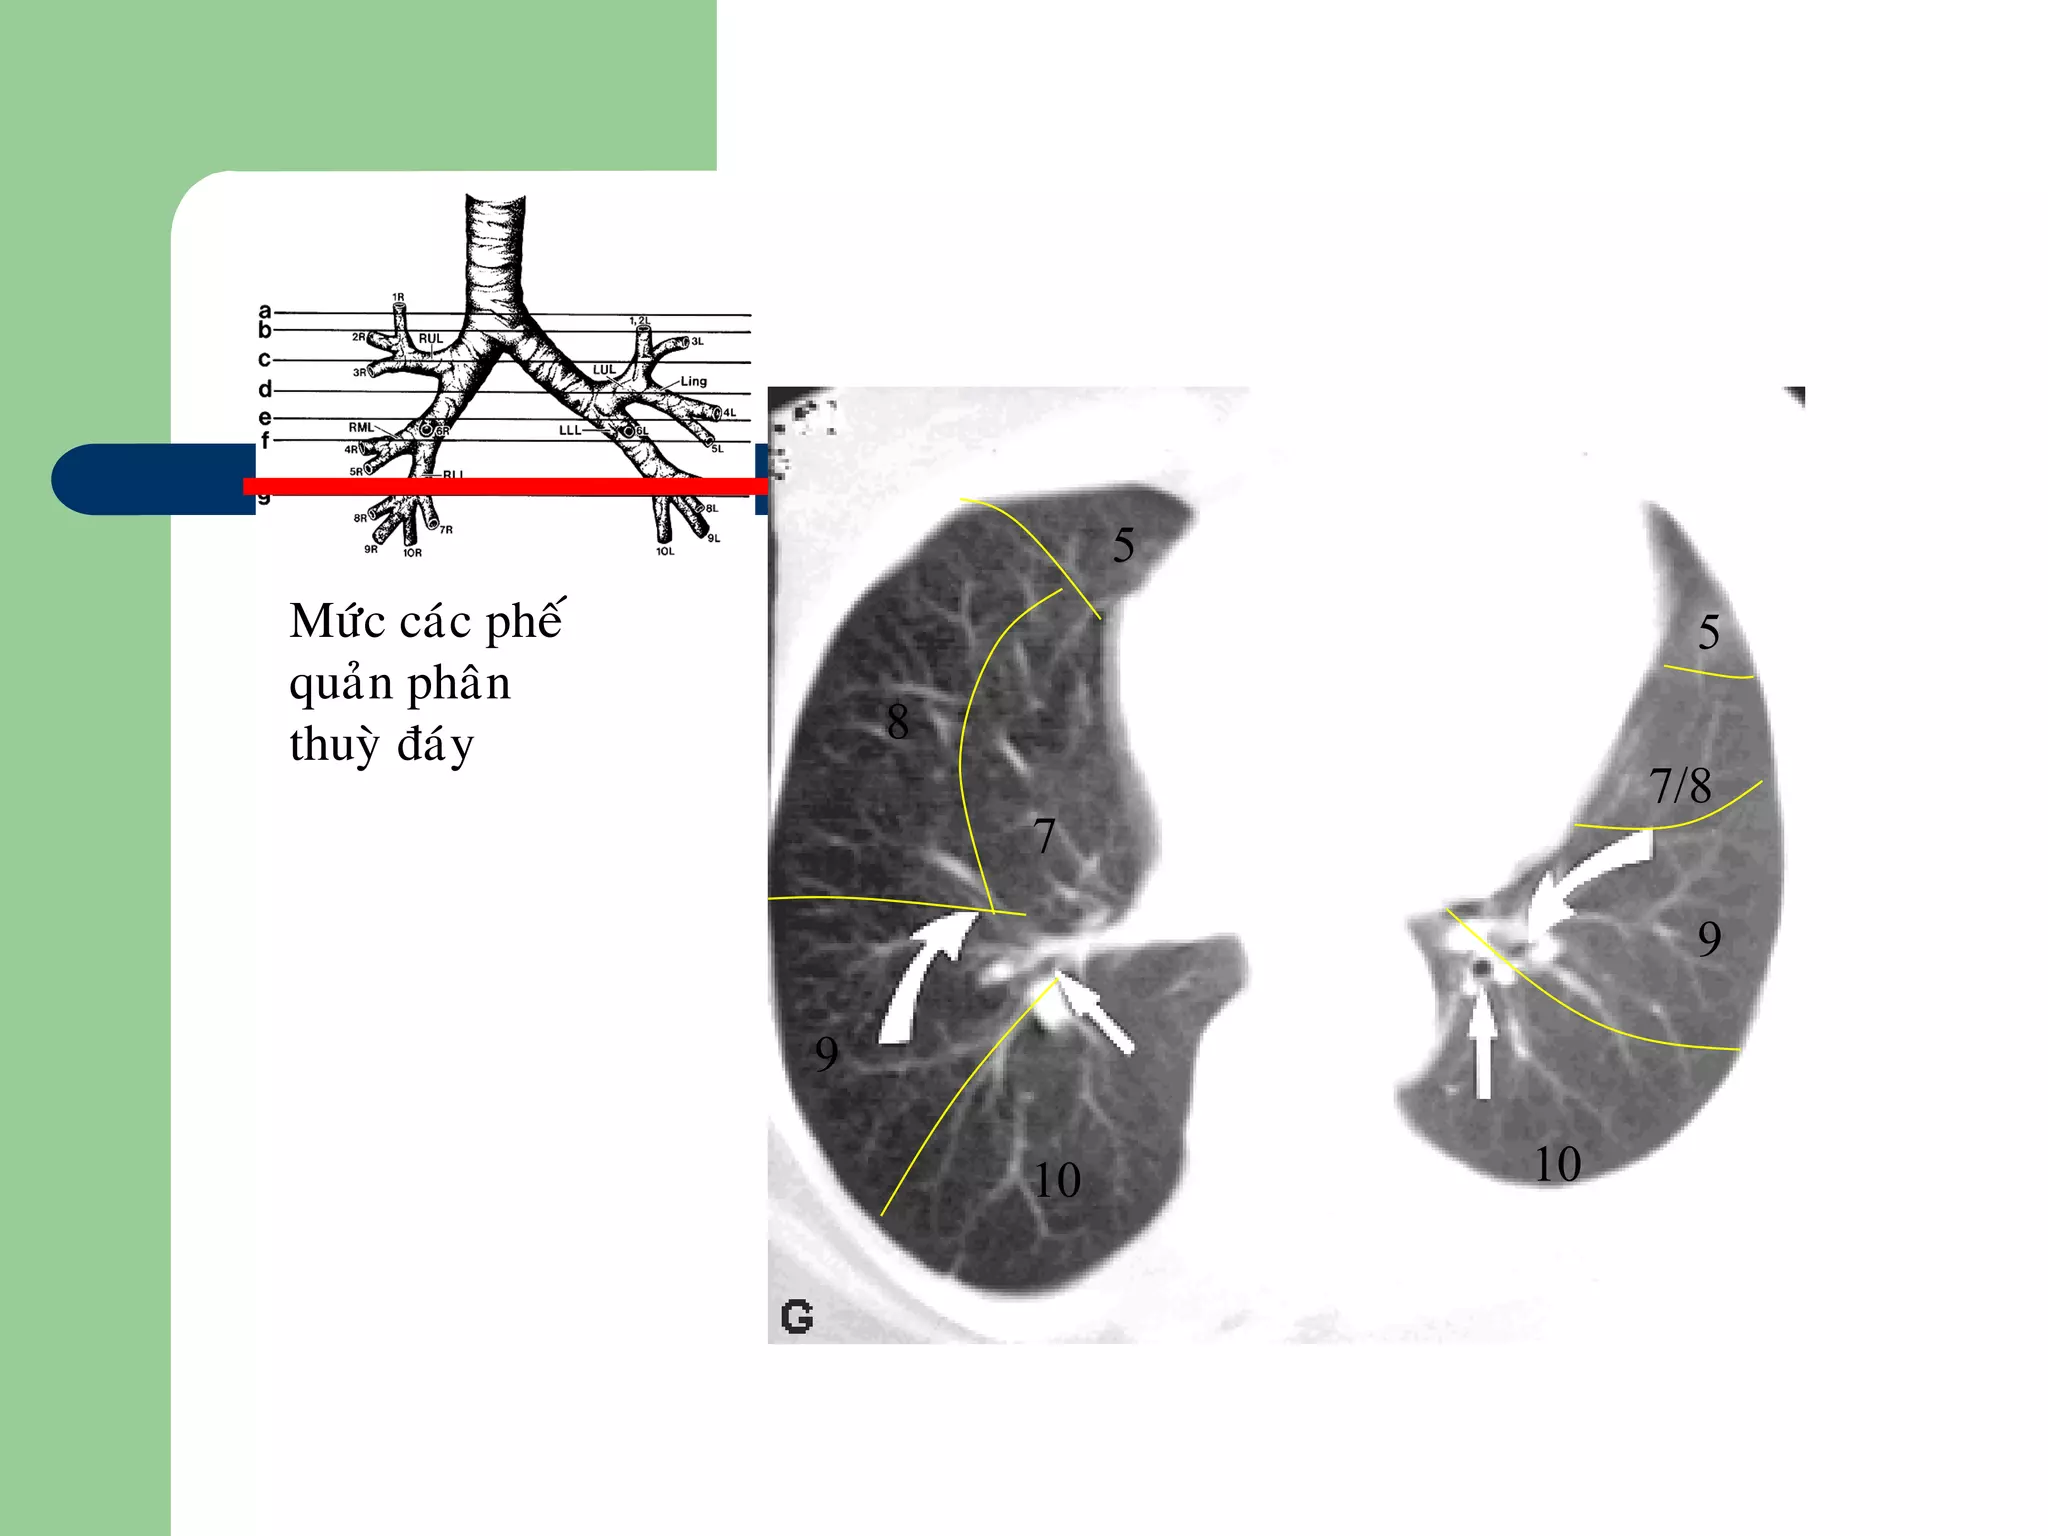

Möùc caùc pheá

quaûn phaân

thuyø ñaùy

10

5

8

9

7/8

7